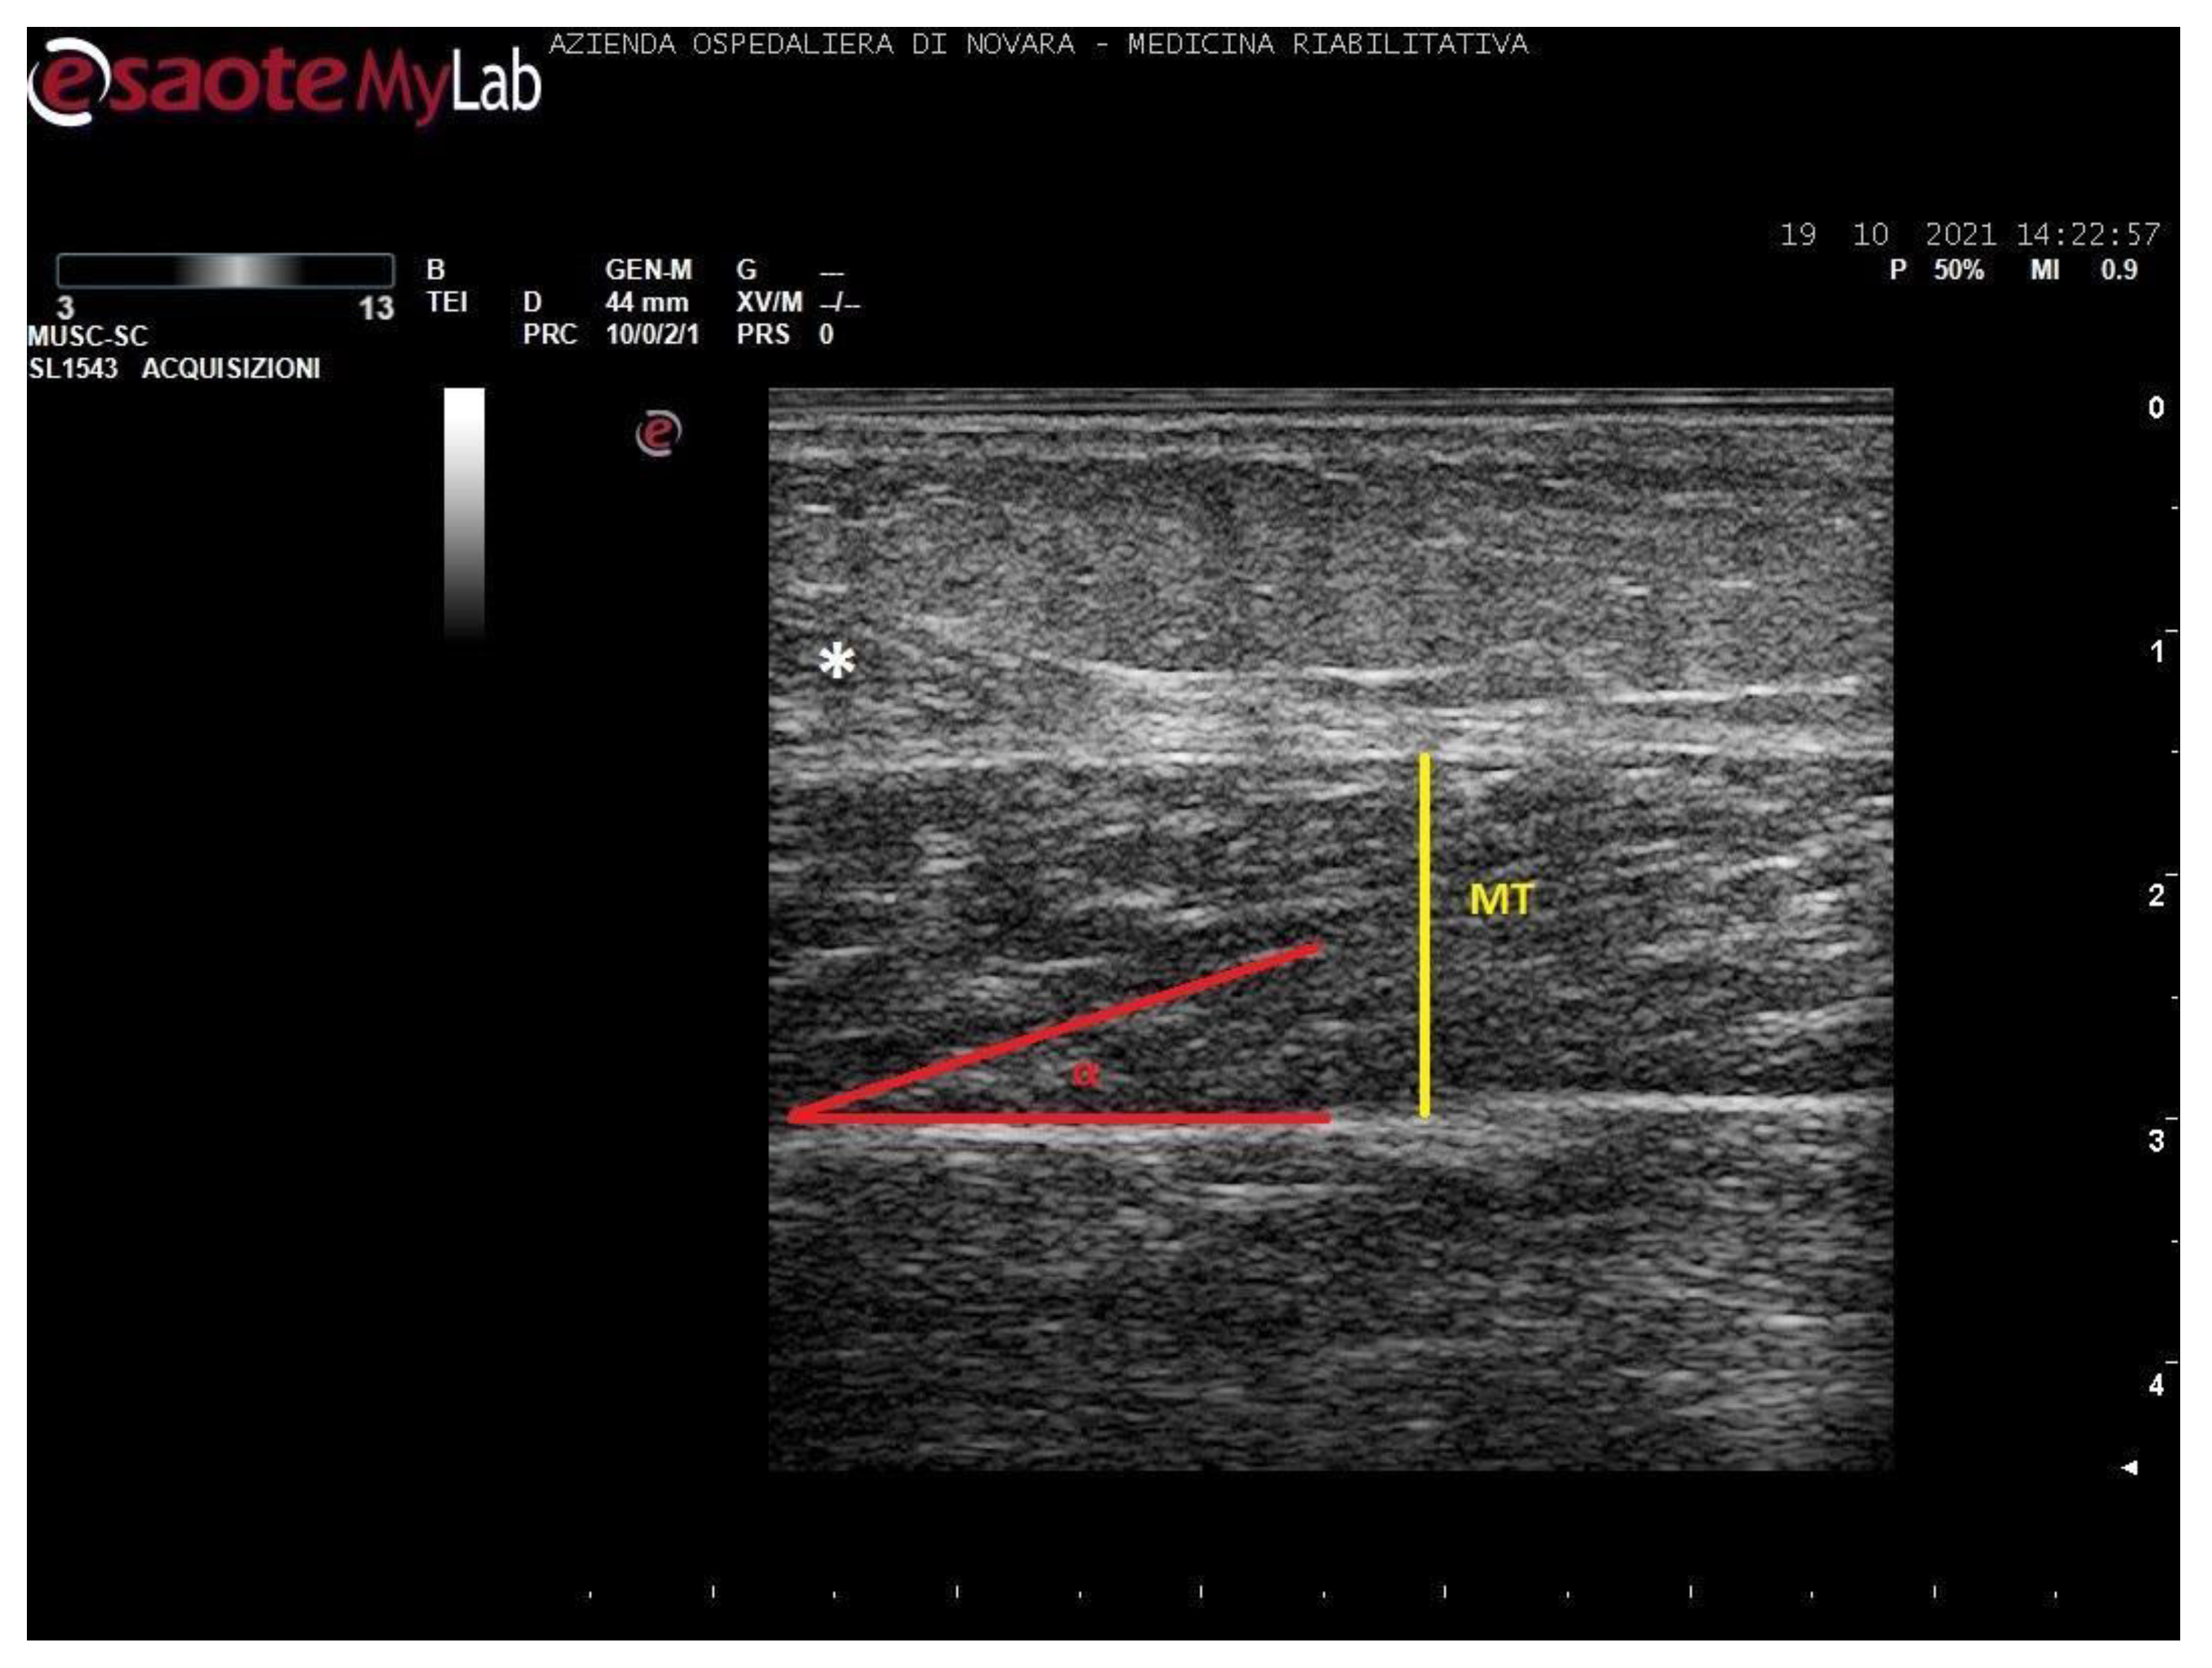

We acquired images of the medial gastrocnemius (MG) and soleus (SOL). Images were processed through the software ImageJ (National Institutes of Health, USA) in order to measure the muscle thickness (MT, cm), the cross-sectional area (CSA, cm2), the pennation angle (α, °), and the mean gray value (MGV, range 0-255). MGV was assessed considering the whole muscle longitudinal section as region of interest (ROI). The gray scale spreads from 0 (black) to 255 (white).

Measurements were taken as shown in Figure 1, Figure 2, Figure 3 and Figure 4.

Figure 2. Ultrasound image of medial gastrocnemius in longitudinal section. In yellow: muscle thickness (MT), in red: pennation angle (α).